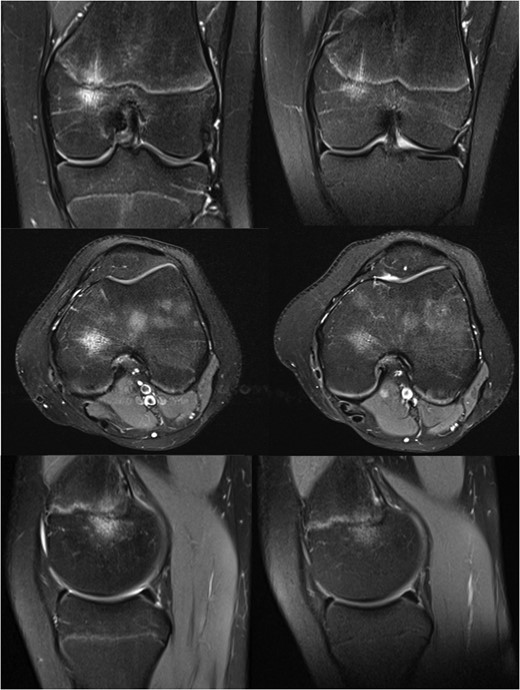

MRI images of the knee at 9 (left) and 13 months (right) after initial injury.

Her symptoms gradually improved without treatment, and with the significant improvement seen on her MRI scan she was eventually discharged from our care fourteen months after her initial injury.

The case described here shows a progression of the FOPE lesion towards resolution that is well correlated with the clinical development experienced by our patient. The story clearly relates to trauma in an active adolescent, and is very similar to that described previously.

This suggests that in this case FOPE was the cause of pain and that our findings support the theory that trauma may play a role its aetiology.

This case is in keeping with the previously described cohort of affected patients and supports the current data suggesting that FOPE is a self-limiting condition that does not require any invasive investigation or management.